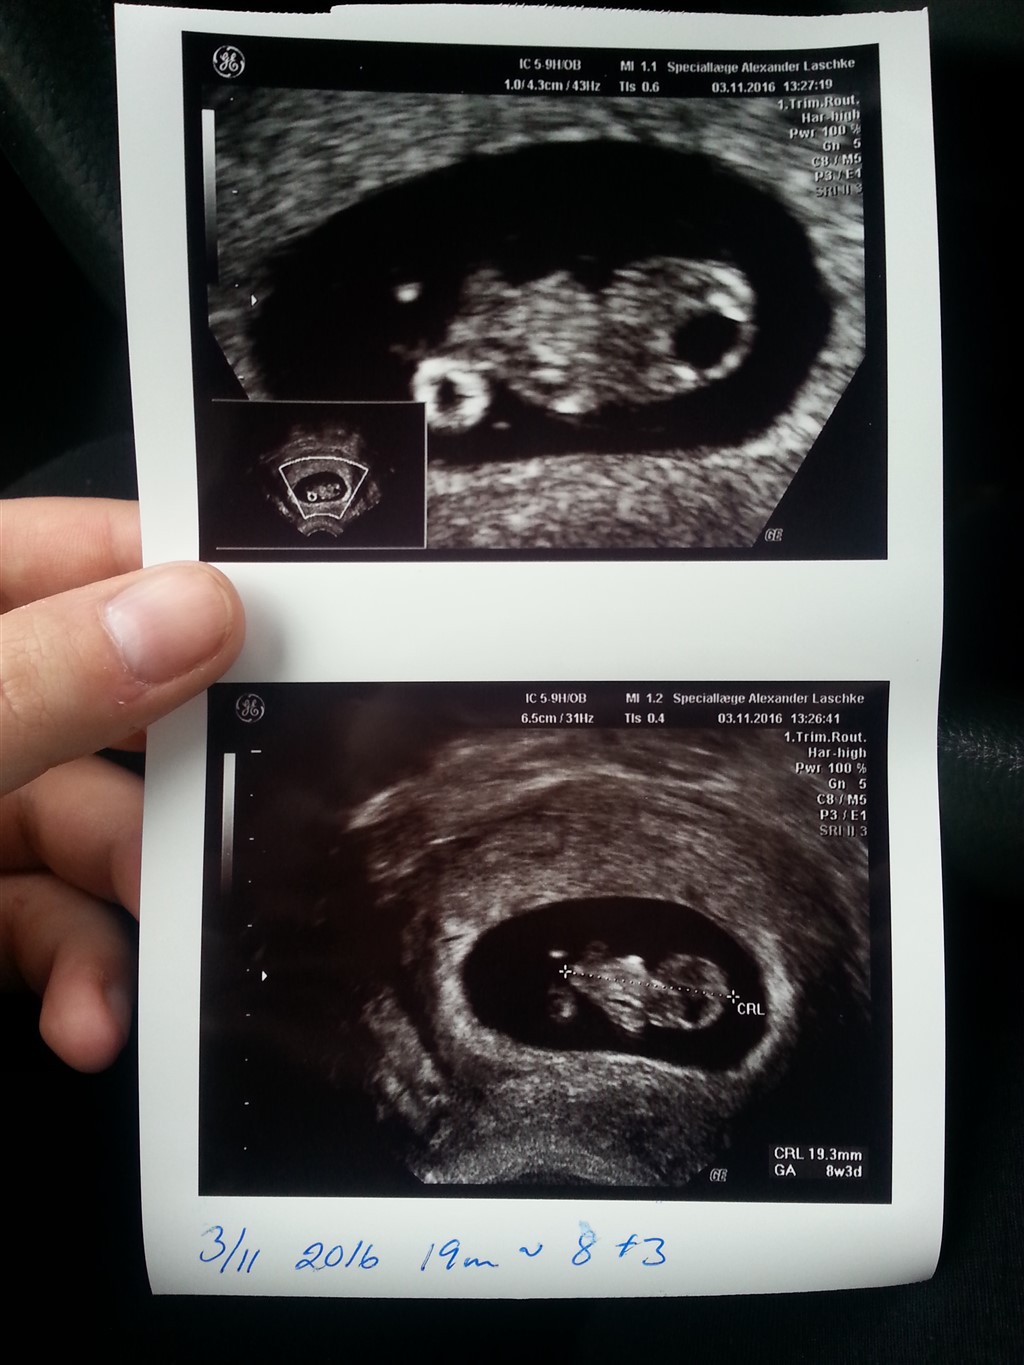

da jeg har pco og haft en meget ustabil cyklus tog jeg til en scanning hvor jeg så rent faktisk finder ud af jeg allerede er 8 uger henne.

og termin blev derfor indtil videre 12 juni.